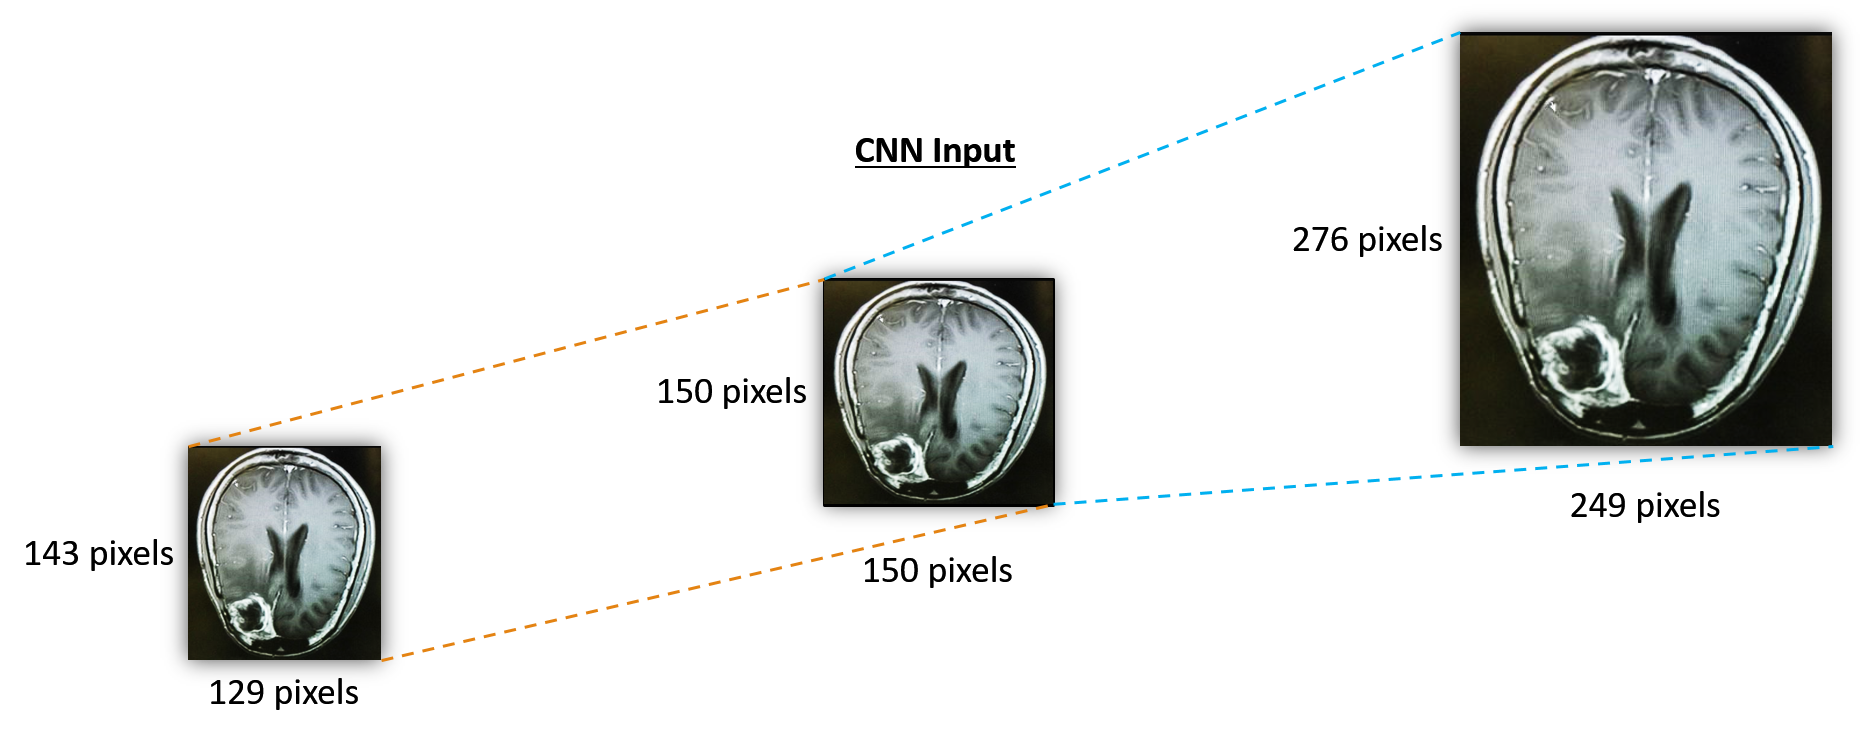

Resizing: It is the process of changing the scale of the images so that all the samples in the training and testing data sets are of the same resolution. This is required because, in the classification models, we must provide input of the same size. The images are resized to 150×150150150150\times 150 pixels using the using Numpy squeeze function for each MRI data, as shown in Fig. 2.

Refer to caption

Figure 2: Example of resizing an MRI image.